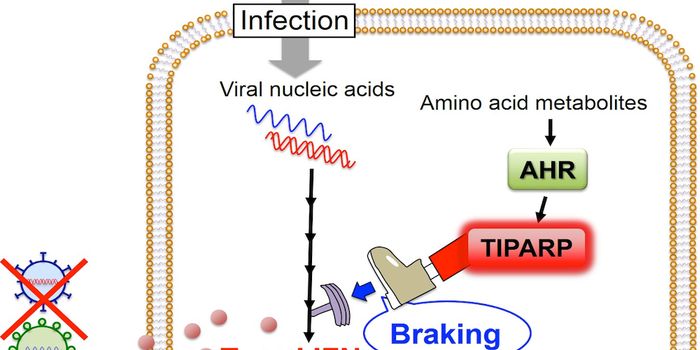

JUL 09, 2016Cell & Molecular BiologyThe aryl hydrocarbon receptor (AHR) was initially characterized as one which mediates the effects of the pollutant dioxi ...